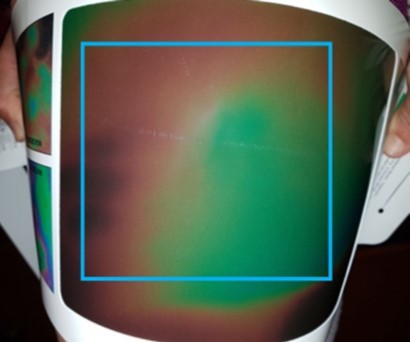

For this analysis, only 80% (approximately) of the area represented by the thermographic photo was taken into account. The colors outside the frame were not included in the analysis (figure 2).

Figure 2.Thermography of the thigh. Blue frame: inside, the area included in the colorimetric analysis.